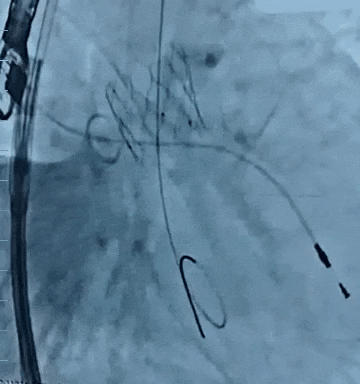

康复大学青岛中心医院林明山教授分享一例“双瓣一站式”高难度VIV病例,深刻展现自膨短瓣在生物瓣衰败VIV中的应用价值。患者83岁男性,于2010年行主动脉瓣置换术、二尖瓣置换术及三尖瓣成形术,现主动脉瓣和二尖瓣生物瓣均出现重度反流,术前超声/CT充分评估后,决定采用经心尖入路,先行主动脉瓣瓣中瓣植入术(TAVR-VIV),顺利送入ScienCrown TAVTA 23mm瓣膜,得益于该款瓣膜短瓣架设计,完全释放后对血流影响小,因此TAVR-VIV术中无需起搏,瓣膜初次释放位置稍浅,部分回收调整瓣膜深度重新释放,即刻造影示瓣膜位置良好,无张力脱钩瓣膜位置稳定,术后TEE示主动脉瓣平均跨瓣压差仅4mmHg。随后行二尖瓣瓣中瓣植入术(TMVR-VIV),经心尖入路植入ScienCrown TAVTF 29mm瓣膜,主动脉根部造影,冠脉显影良好无瓣周漏,术后TEE示二尖瓣平均跨瓣压差仅1mmHg。

双瓣VIV术后最终造影